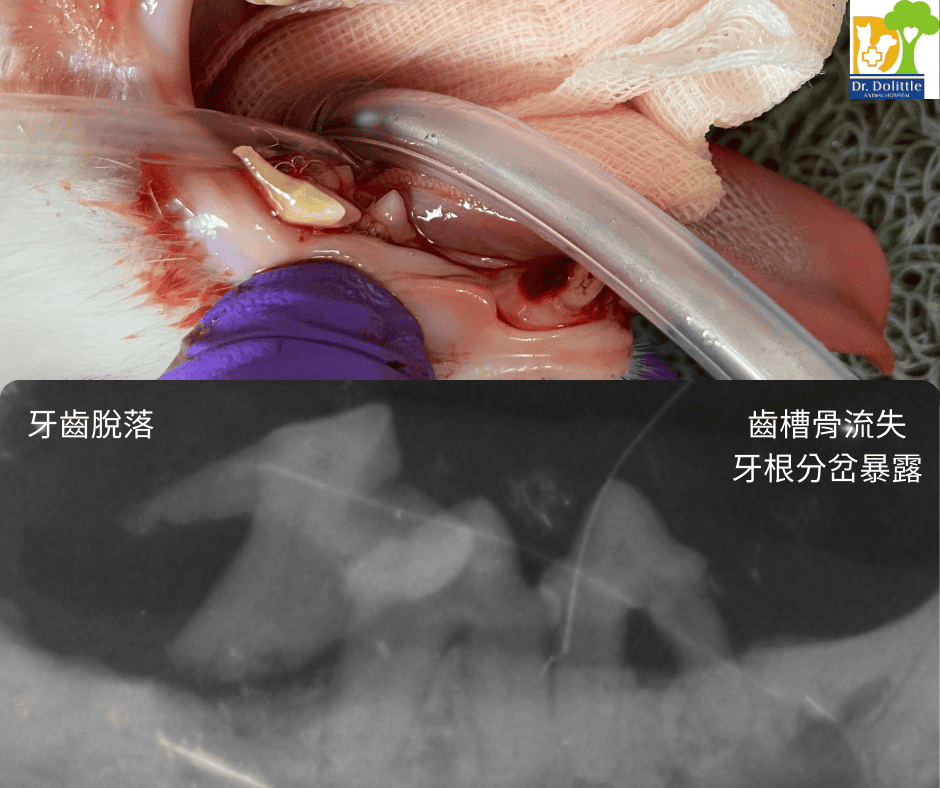

4. 拔牙/牙周治療

• 若 X 光顯示牙齒無法保留(如嚴重牙周病、牙根尖膿腫、貓咪齒吸收),需進行拔牙手術。

• 拔牙傷口依據位置、大小進行傷口縫合,傷口較大會進行牙齦皮瓣縫補。